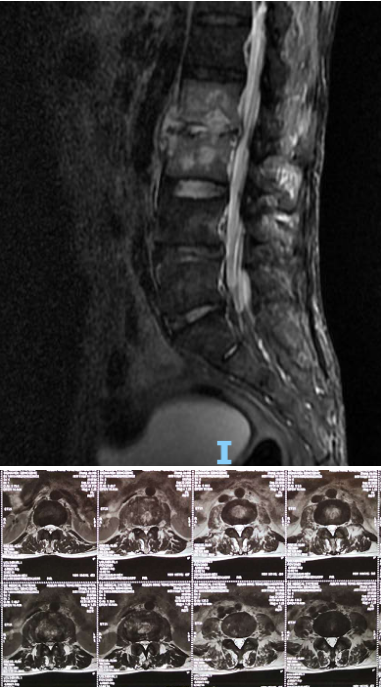

术前腰椎MRI

患者张某某,男性,51岁,云南曲靖人。患者自诉1月前不明显诱因出现腰部疼痛,并且进行性加重,活动后明显加重,在当地县中医院就诊行针灸等治疗无好转,后到县医院行腰椎MRI等检查显示:腰2、3椎体及椎旁软组织异常信号,结核、其他感染病变不能排除。后为进一步诊治,到昆明某医院就诊并住院治疗,行“L3椎体穿刺活检术”,病理报告提示:慢性炎性细胞浸润,诊断为:腰2、 3椎体感染,予静脉应用抗生素抗感染等治疗一周,出院后继续在当地继续抗感染治疗。

患者出院后感腰部疼痛持续加重,到少妇色情 门诊就诊,以“腰椎感染”收住入院。患者发病后腰椎CT及MRI均提示腰2-3椎间隙变窄,椎板破坏,综合以上资料诊断”腰椎结核”。入院后经口服四联抗结核药物治疗3周,患者自觉腰部疼痛减轻,午后无发热及盗汗后,在全麻下行颈后路病灶清除、椎间植骨、椎弓根钉棒系统内固定术。手术顺利,术后继续抗结核治疗。患者恢复顺利,术后1周下床活动,无特殊不适。术后2周拆线、出院,院外继续口服抗结核药物治疗,定期门诊复查。